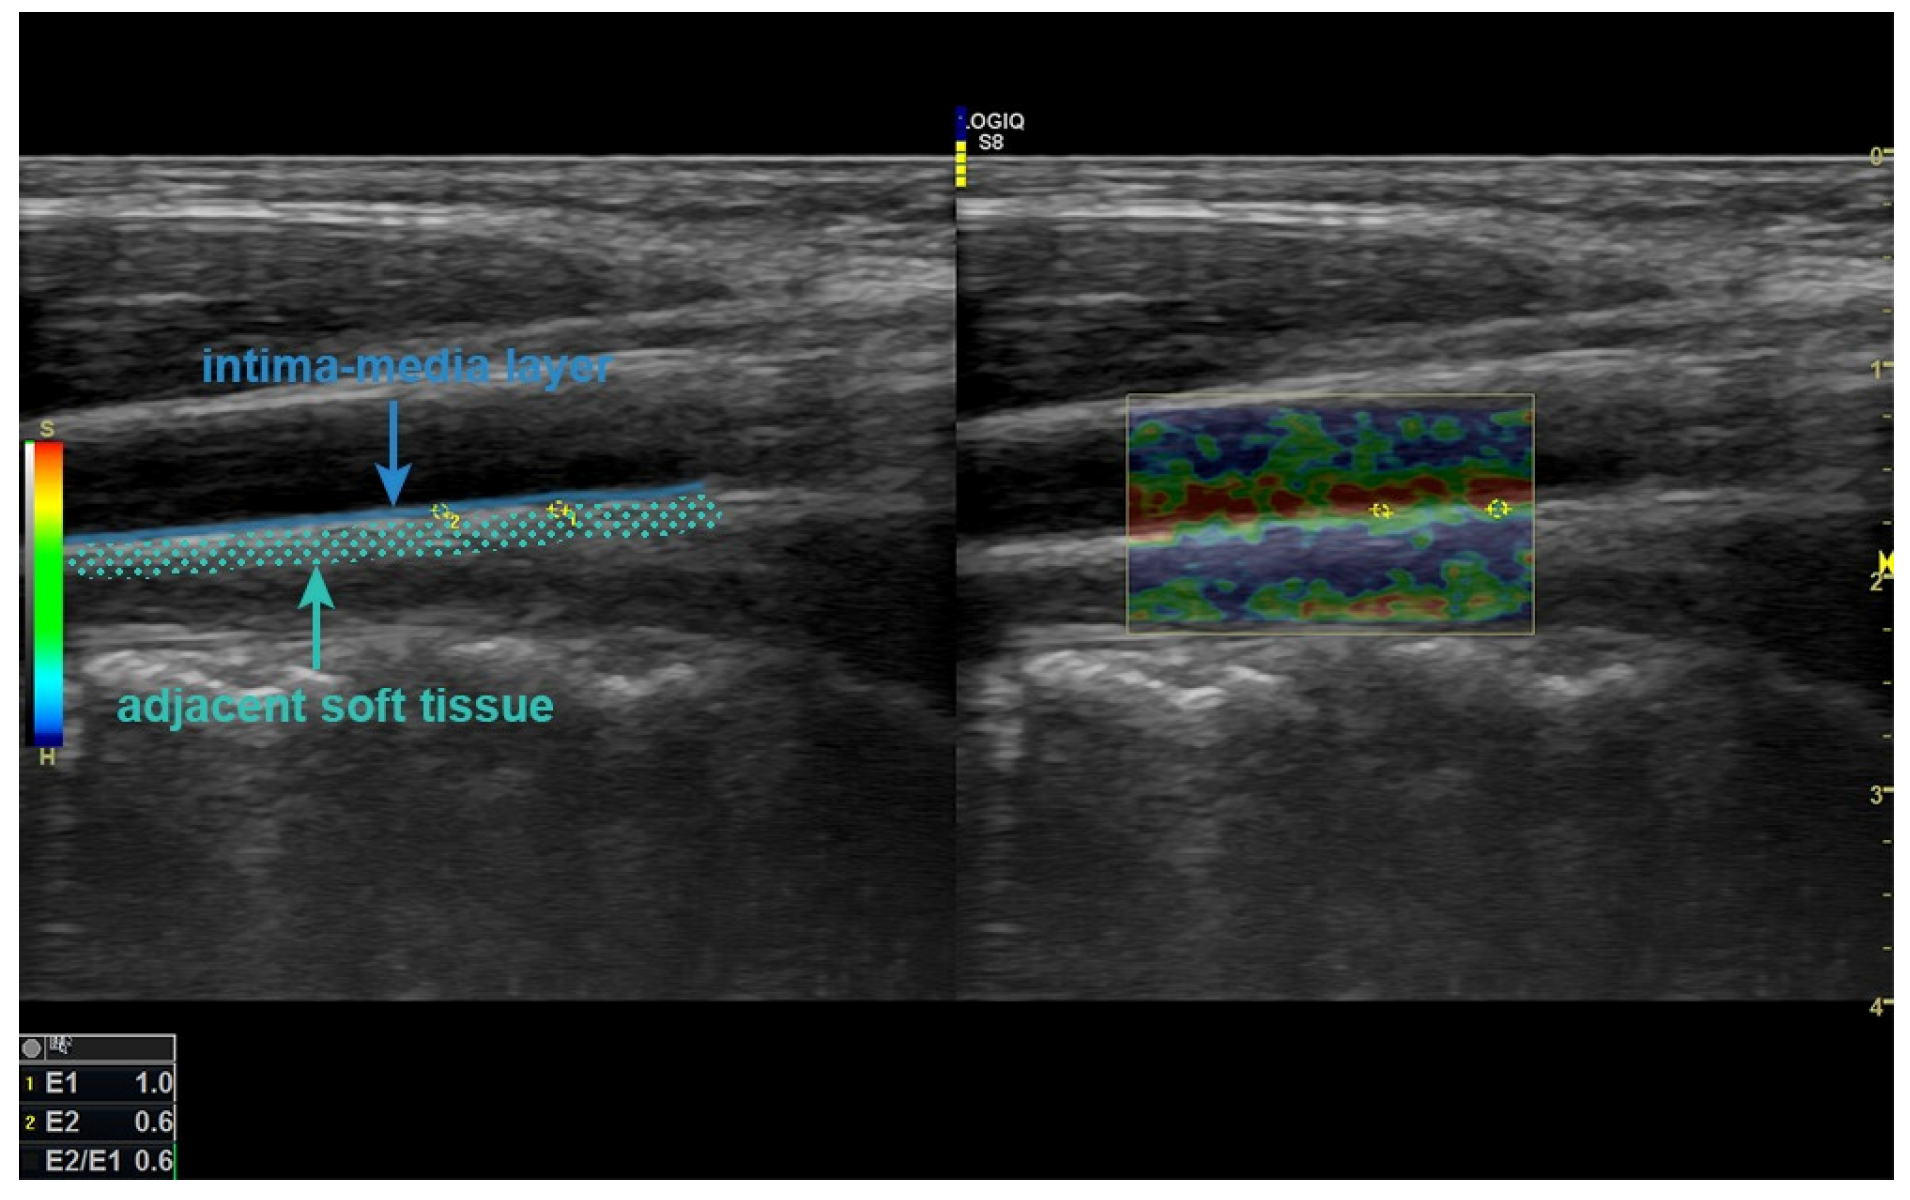

2.1. B-Mode Ultrasonographic and Elastography Evaluation